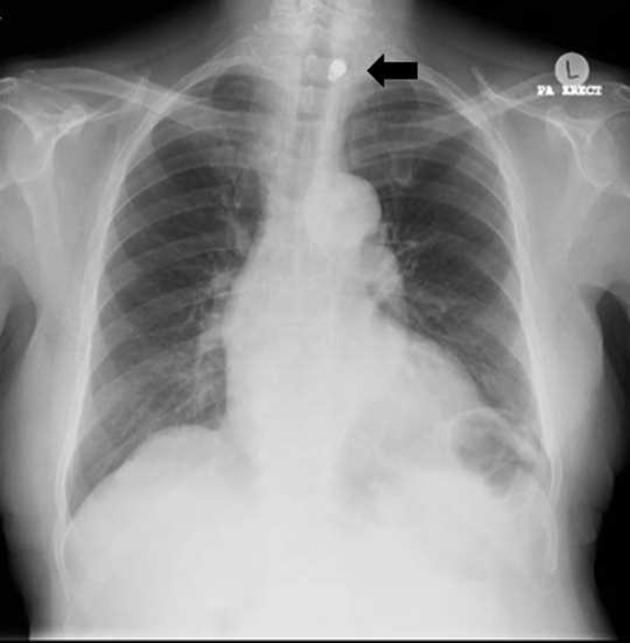

Wireless capsule endoscopy was introduced over a decade ago and is now a widely used tool in the investigation of gastrointestinal pathologies. Despite its ubiquity, the full profile of indications, contraindications and complications is still being developed. Metal artefact reduction is a software technique which can significantly reduce the artefact produced by metallic objects on CT scans. This case exemplifies a rare but noteworthy complication of capsule endoscopy and highlights a novel application of metal artefact reduction.